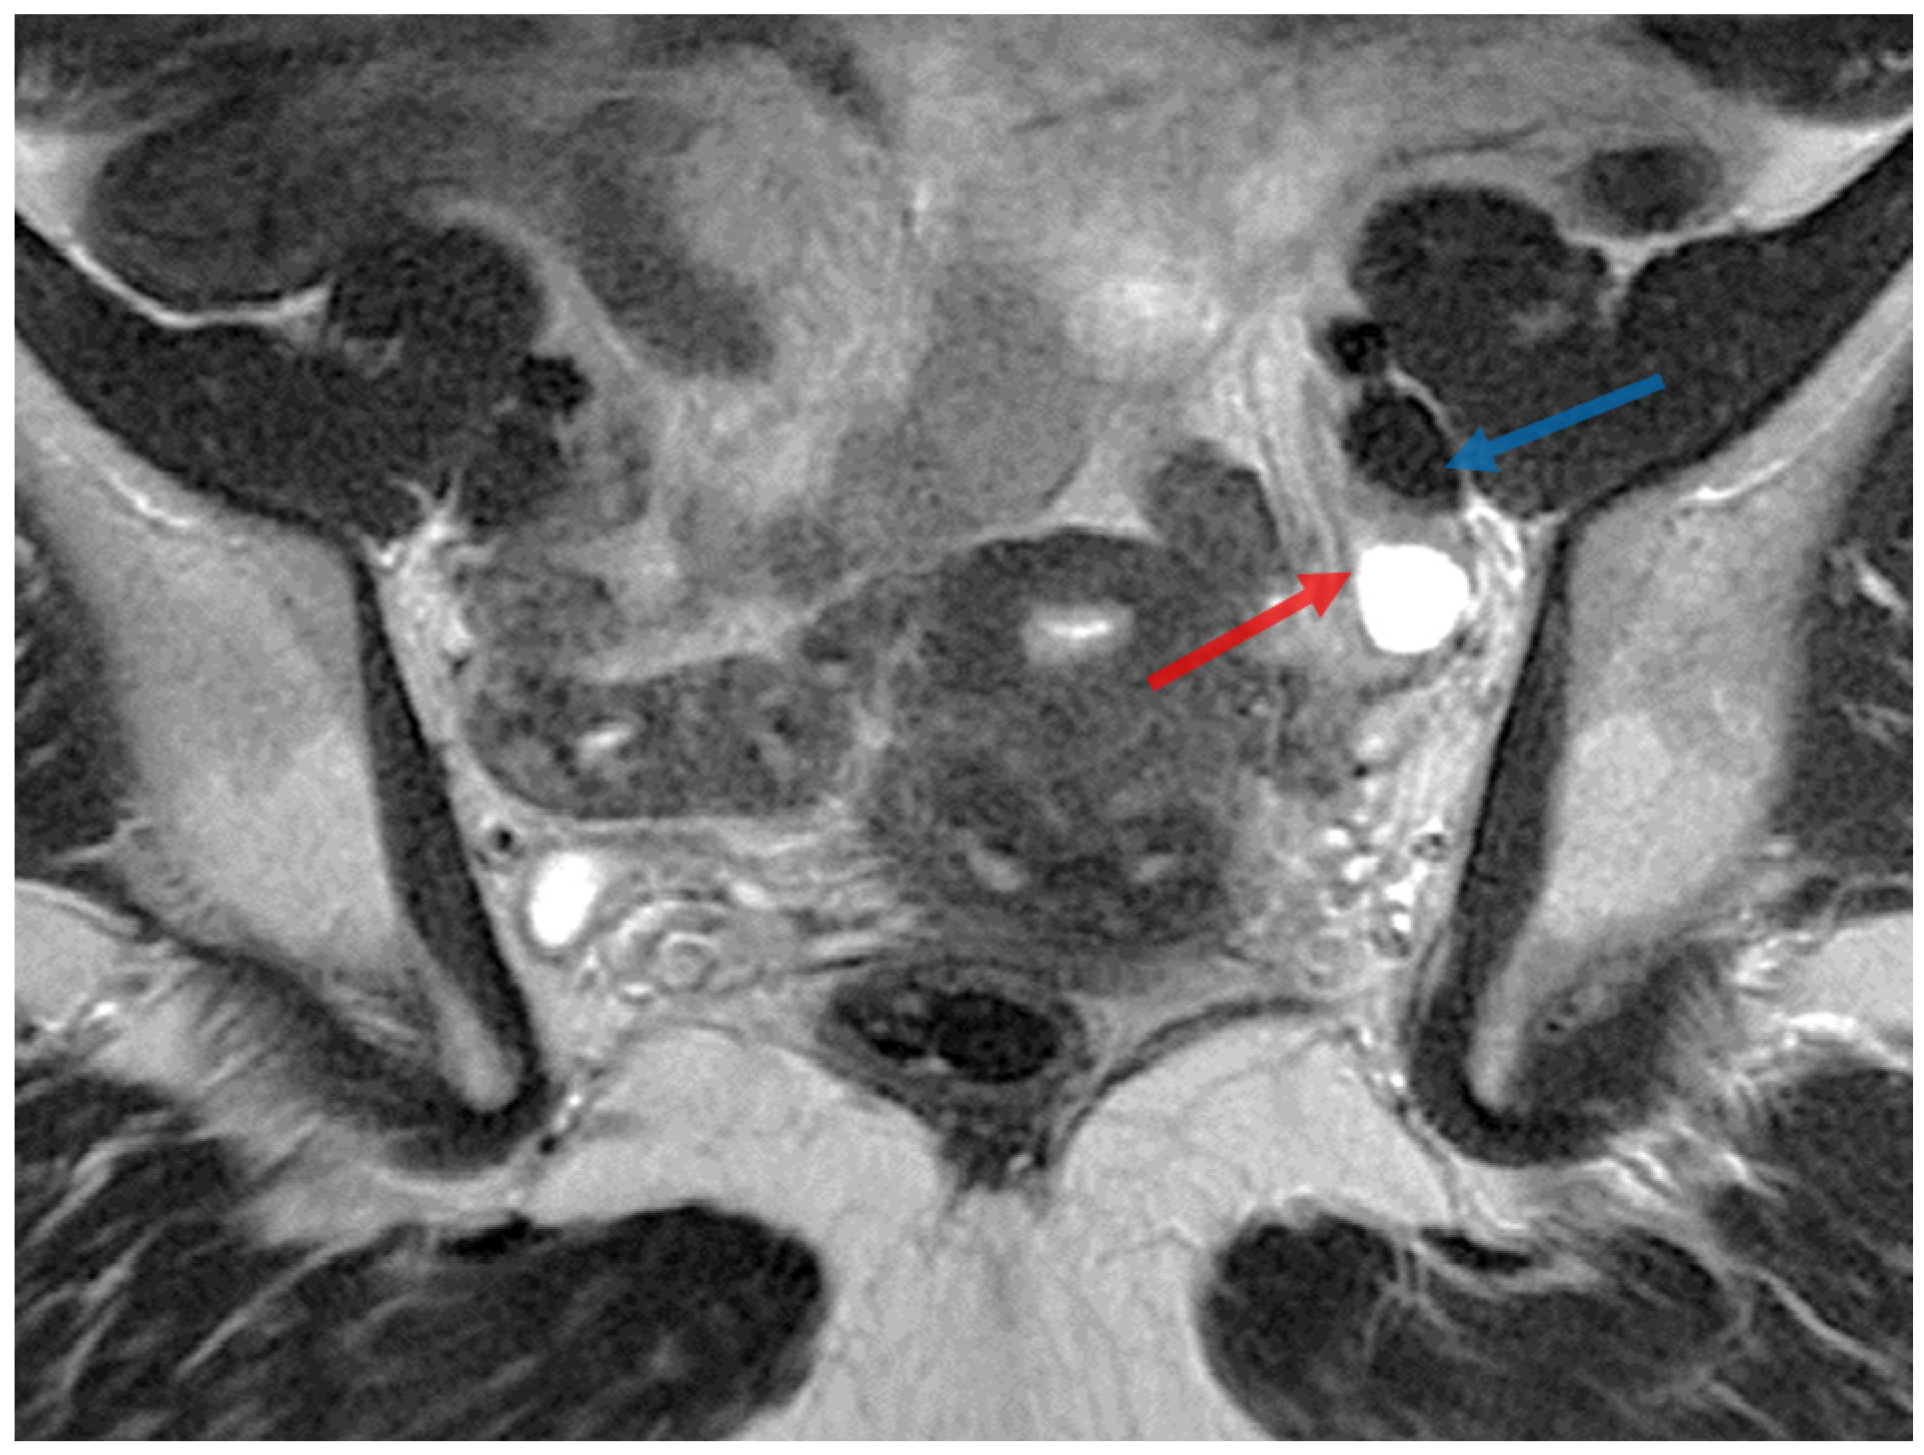

2. Case Presentation